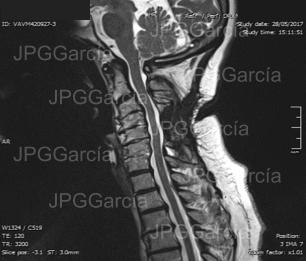

Fotografía trasquirúrgica para exposición dural y colocación de tornillos y barras cervicales posterior para tratamiento de conducto cervical estrecho

Fotografía trasquirúrgica para exposición

dural y colocación de tornillos y barras

cervicales posterior para tratamiento de

conducto cervical estrecho